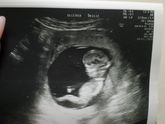

13 декабря 2019 14:23 Вот и я с первого скрининга. Счастью нет предела. Очень долгожданный малыш. Муж подарил цветы ? видимо дождался доказательств). 7см от макушки до копчика?